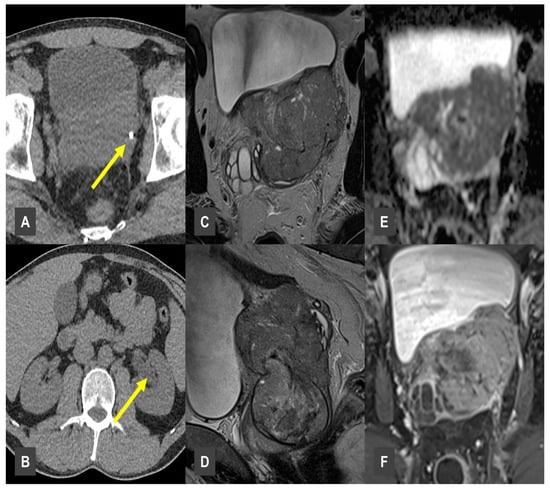

Prevalence and Significance of Incidental Findings in Multiparametric Magnetic Resonance Imaging of the Prostate

by David Weiß, Arne Bischoff, Michael Brönnimann, Matteo Haupt and Martin Maurer

Tomography 2025, 11(11), 118; https://doi.org/10.3390/tomography11110118 - 23 Oct 2025

Objective: This study aims to assess the prevalence of clinically significant incidental findings as well as incidental findings of minor clinical significance in multiparametric MRI (mpMRI) of the prostate. Materials and Methods: A retrospective analysis was conducted on 607 male patients (mean age: [...] Read more.

Objective: This study aims to assess the prevalence of clinically significant incidental findings as well as incidental findings of minor clinical significance in multiparametric MRI (mpMRI) of the prostate. Materials and Methods: A retrospective analysis was conducted on 607 male patients (mean age: 72 years) who underwent prostate MRI between 2018 and 2023 at a single center. Two radiologists reviewed in consensus the scans for incidental findings during multiparametric MRI of the prostate. The findings were classified according to their clinical relevance, organ group and patient age. Results: Among 607 male patients (mean age: 72 years), 665 incidental findings were identified in 410 patients (67.5%; 95% CI 63.7–71.1). This corresponds to an average of 1.10 incidental findings per patient across the entire cohort. Of the 665 findings, 12 (1.8%; 95% CI 0.9–3.1) were classified as clinically significant. These included cases of sarcoma, rectal carcinoma, hydronephrosis, aortic aneurysm, avascular necrosis of the femoral head and high-grade disc protrusion with spinal canal stenosis and diverticulitis. Conclusions: Our data indicate that incidental findings are common in prostate mpMRI examinations; however, only a small proportion are clinically significant. This underscores the need for awareness of such findings, while avoiding unnecessary follow-up for those without clinical relevance. Full article

Show Figures

Figure 1